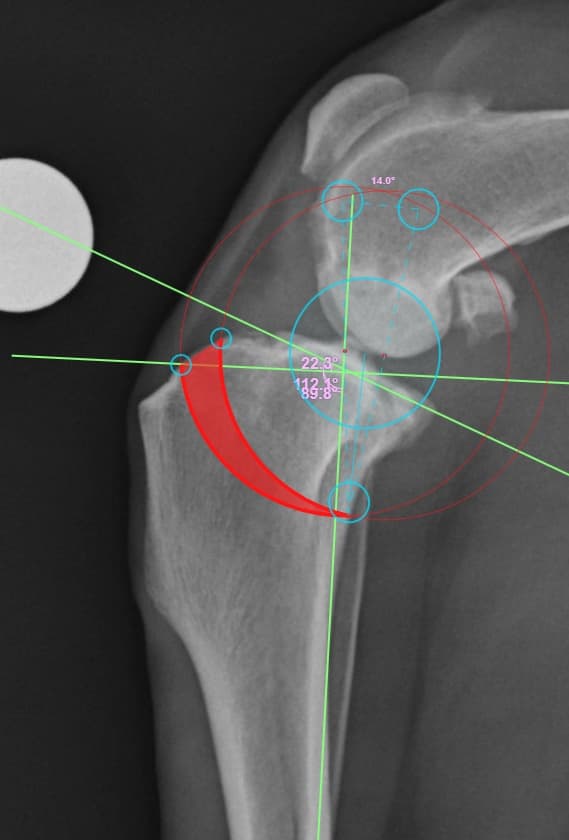

정형외과 전공의 수의사가 직접 수술합니다.

02C-arm을 통해서 좀 더 섬세한 정형외과 수술을 진행하고, 본원에서는 외과적 침습을 최소화 하는 중재적 시술 (기관 협착, 동맥관개존증(PDA), SUB 등)을 진행하고 있습니다.

12정교한 정형외과 도구를 사용하여 신속 정확한 정형외과 수술이 가능

13수술 중 골절 상태 혹은 이식물 적용 후 상태 등 육안으로 명확히 확인하기 힘든 상태를 X-ray 확인하여 정확한 수술 결과를 만들어 내는 것이 가능